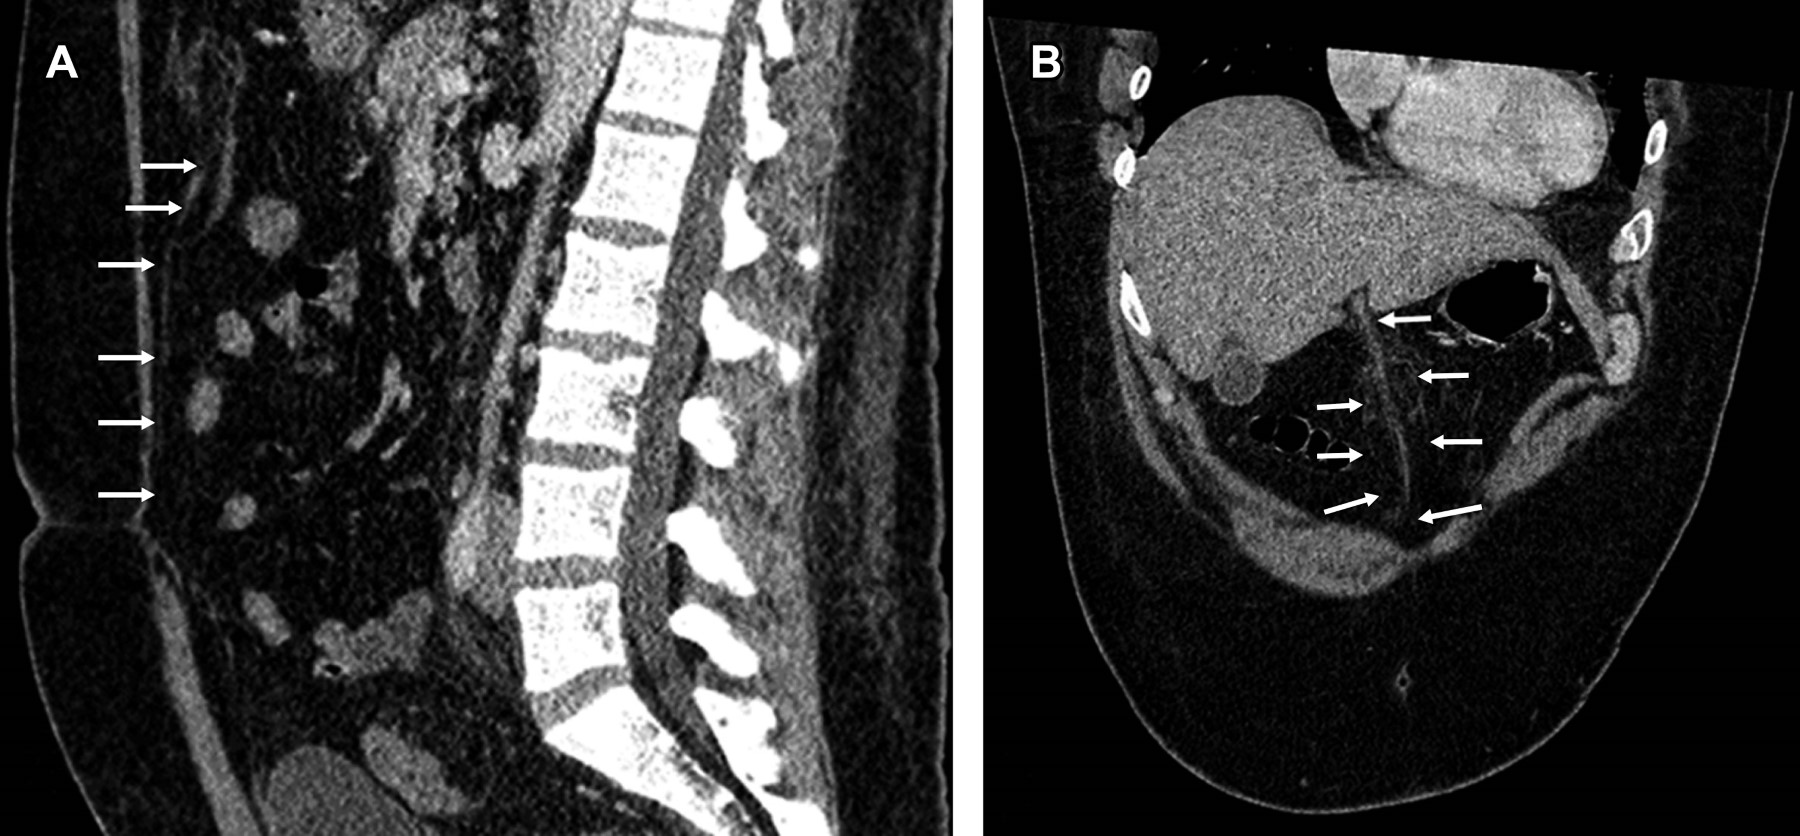

Se trata de paciente masculino de 34 años, inicia cinco días previo a su ingreso con dolor en fosa iliaca izquierda y dolor inguinal bilateral, acompañado de fiebre, escalofríos y diaforesis. A la exploración física a su ingreso presenta peristalsis disminuida, rigidez abdominal a la palpación y signo de Blumberg positivo. El laboratorio reportó: leucocitos de 15 × 109/L, hemoglobina de 15.6 g/dL, neutrófilos segmentados 11.54%, neutrófilos en banda 61%; examen general de orina (EGO): proteínas y cuerpos cetónicos presentes, leucocitos 2 × campo, bacterias escasas y sangre ausente. La tomografía computarizada abdominopélvica simple y con contraste IV mostró diverticulitis sigmoidea, Hinchey 1a (Figura 1). Cuatro días después manifiesta dolor abdominal irradiado a epigastrio, la tomografía de control simple y contraste IV (Figuras 2 y 3) mostró cambios inflamatorios en el recorrido completo del ligamento Teres, altamente sugestivos de trombosis, así como vesícula biliar reactiva (pared gruesa) y adenitis mesentérica, discreto líquido libre abdominal y derrame pleural bilateral. El paciente recibió tratamiento conservador y fue dado de alta al séptimo día.

Figura 3